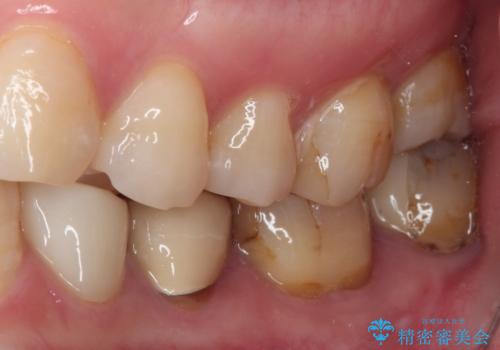

- 見た目の不揃いなセラミックと、痛みを感じる歯を気にして来院された患者様です。

右上の歯は噛んだときに何カ所か痛みを感じるとのことで、診査したところ第二小臼歯が患歯と疑われました。

患者様は他の歯にも痛みを感じるとおっしゃっていましたが、そのような所見が認められなかったため、まずは第二小臼歯を処置し、その痛みが引いた後に再診査することとしました。

痛みが引いた後、不揃いな見た目で気になっていた左下の奥歯とともにオールセラミッククラウンにて補綴治療を行うこととしました。